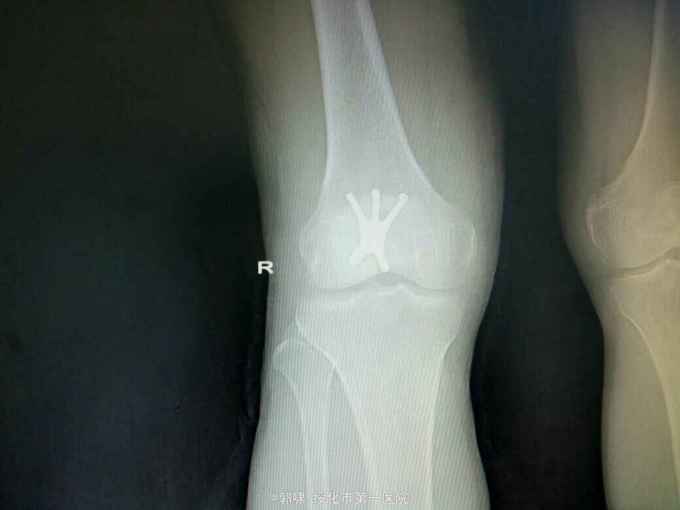

左膝关节摔伤,肿胀,畸形,活动受限一小时。收入院。患者于一小时前滑倒摔伤。当即倒地,左膝关节肿胀,畸形不能行走。门诊拍片示:左膝关节髌骨骨折,断端移位。门诊以左髌骨骨折收入院。

左膝关节肿胀,局部畸形,不能下地行走。浮髌试验阳性。拍片示:左髌骨骨折。

诊断:左髌骨骨折。立即予以腰麻下行切开复位内固定术。术中复位骨折,缝合筋膜,冰水浸泡髌骨爪约10分钟。待髌骨爪变软。选取合适大小的髌骨爪。应用记忆合金髌骨爪内固定。立即用40°温盐水热敷局部。使记忆合金加速抓紧。环抱。缝合爪齿二道,防止脱落。缝合关节囊,韧带组织。术毕。

应用记忆合金髌骨爪内固定髌骨骨折。手术时间基本在20----30分钟内都可以完成。局部损伤小。固定牢靠,确实。患者二个月就可以下地负重活动。具体手术技巧。一是髌骨爪提前用冰盐水侵泡10分钟左右。待记忆合金变软即可使用。二。固定牢靠后立即用40°温盐水热敷。使其快速抓紧。三,缝合爪齿,防脱。四如有粉碎,小的骨块可以缝合筋膜固定。有大骨块,最好环扎钢丝,或穿针固定,有时穿骨隧道钢丝捆扎。效果也不错。只要做到以上几点。安全无忧了!以下是以前做的片子。可以看一看。